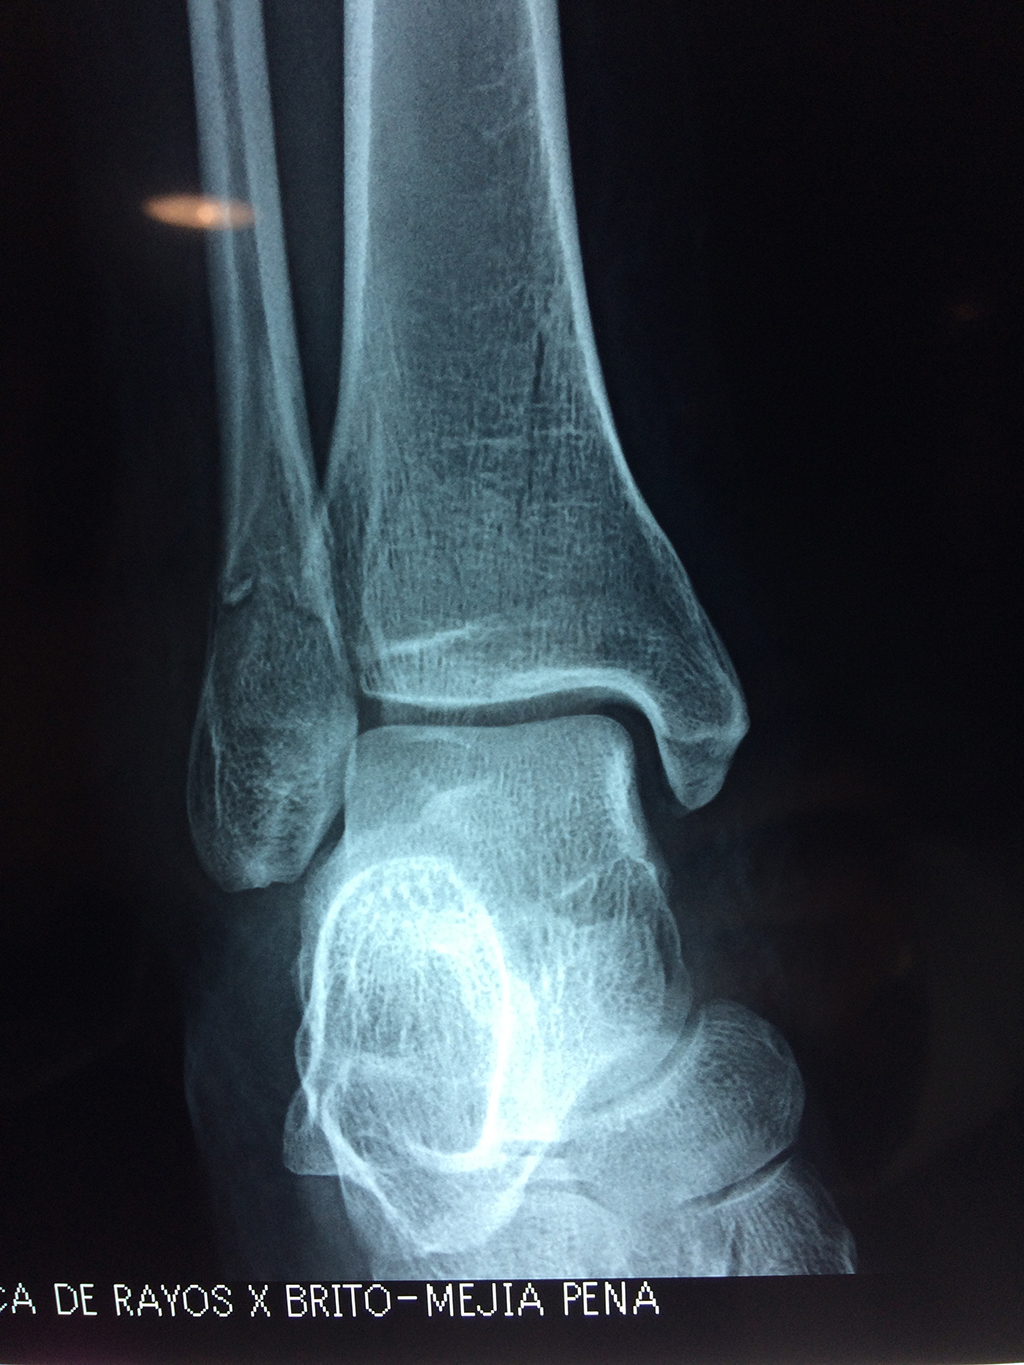

Cirugías de Tobillos

Una fractura de tobillo es la rotura de uno o más de los huesos del tobillo. Estas fracturas pueden ser:

Cuando se necesita cirugía, es probable que esta implique el uso de clavijas de metal, tornillos o placas para sostener los huesos en su lugar mientras la fractura se consolida. Los elementos de soporte pueden ser temporales o permanentes.